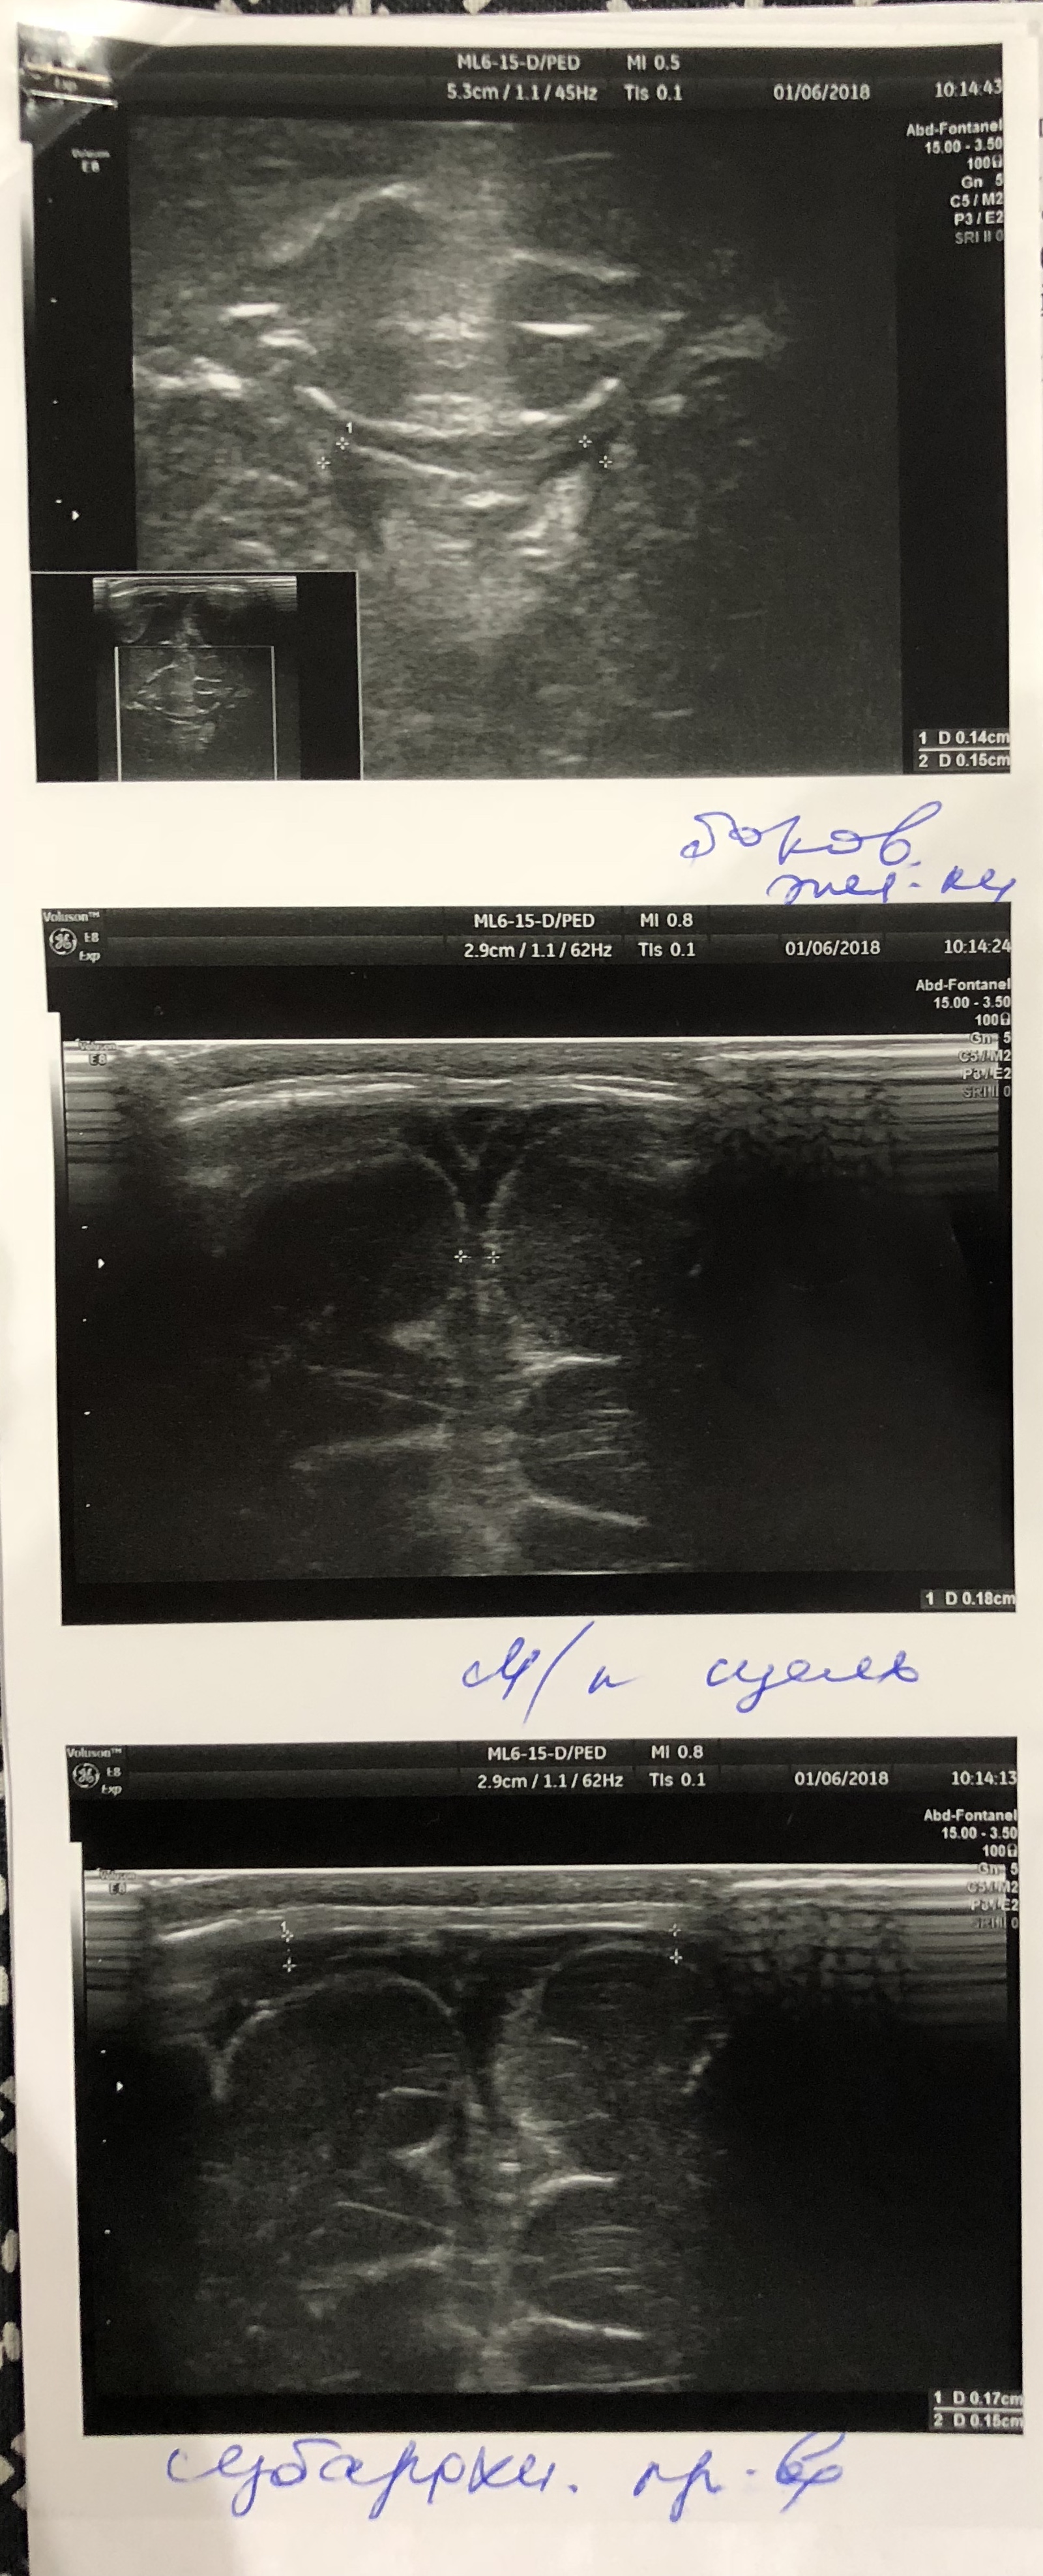

Ходили на НСГ, показало увеличение ЛСК по Вене Галена 20 см/с . Так же обнаружили эхопризнаки сочетанного расширения наружного и внутреннего ликворных пространств (БЖ и САП) . Значения: САП - 7,5 мм БЖ - Левый (передний рог - 5,6 мм, тело - 6 мм) - Правый (передний рог - 5,8 мм, тело - 6,3 мм) Были у офтальмолога, проверяли глазное дно . Все в норме .

Венозный компонент: кровоток в вене Галена не изменен ЛСК =16,8 см/сек (выше возрастной нормы, угрожаем по развитию гипертензионно-гидроцефальному синдрому)